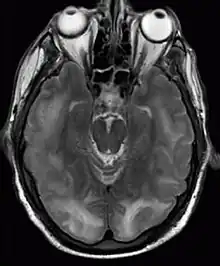

Posterior reversible encephalopathy syndrome visible on magnetic resonance imaging as multiple cortico-subcortical areas of T2-weighted hyperintense (white) signal involving the occipital and parietal lobes bilaterally and pons.

The diagnosis is typically made with magnetic resonance imaging of the brain. The findings most characteristic for PRES are symmetrical hyperintensities on T2-weighed imaging in the parietal and occipital lobes; this pattern is present in more than half of all cases.[1][3] FLAIR sequences can be better at showing these abnormalities.[4] Some specific other rare patterns have been described: the superior frontal sulcus (SFS) watershed pattern, a watershed pattern involving the entire hemisphere (holohemispheric), and a central pattern with vasogenic oedema in the deep white matter, basal ganglia, thalami, brainstem and pons.[1][3] These distinct patterns do not generally correlate with the nature of the symptoms or their severity, although severe edema may suggest a poorer prognosis.[1] If the appearances are not typical, other causes for the symptoms and the imaging abnormalities need to considered before PRES can be diagnosed conclusively.[4] In many cases there is evidence of constriction of the blood vessels (if angiography is performed), suggesting a possible overlap with reversible cerebral vasoconstriction syndrome (RCVS). Diffusion MRI may be used to identify areas of cytotoxic edema caused by poor blood flow (ischemia) but it is not clear if this prognostically relevant.[1][4] Abnormal apparent diffusion coefficient is seen in about 20% of cases.[4]